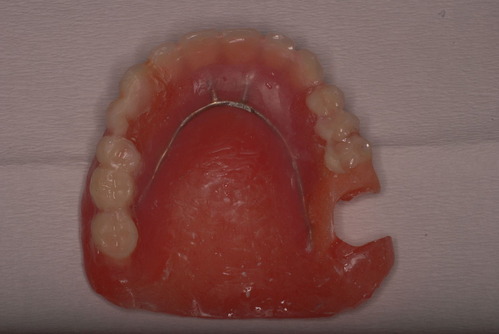

写真の方の高額な入れ歯を拝見するとまず喉の方向の入れ歯の位置が悪く吸着できていない。クラスプと言われる金属の歯を掴むものの形と材料も?でした。全体的に入れ歯のマージンを頬の筋肉で保持できるような形にできていないために吸着が悪いのです。

ですから、全然使用していない安い保険の義歯を使い修理して動かず、痛まず、咬めるようにしてあげると信用絶大になるのです。

写真の入れ歯はボロボロの保険の入れ歯を何とか修理してお渡ししたものです。その後電話で尋ねましたが痛くもなく初めてご飯を食べられるようになったということでした。